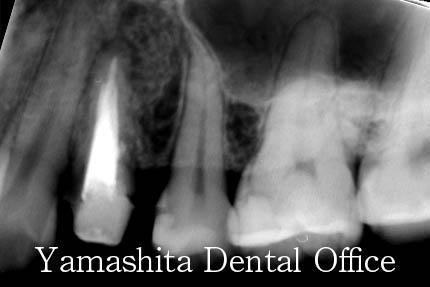

初診時に拝見しましたときは、歯ぐきがパンパンに晴れている状態でした。

根管治療後、腫れや症状は治まり、問題なく病巣は治ってきています。